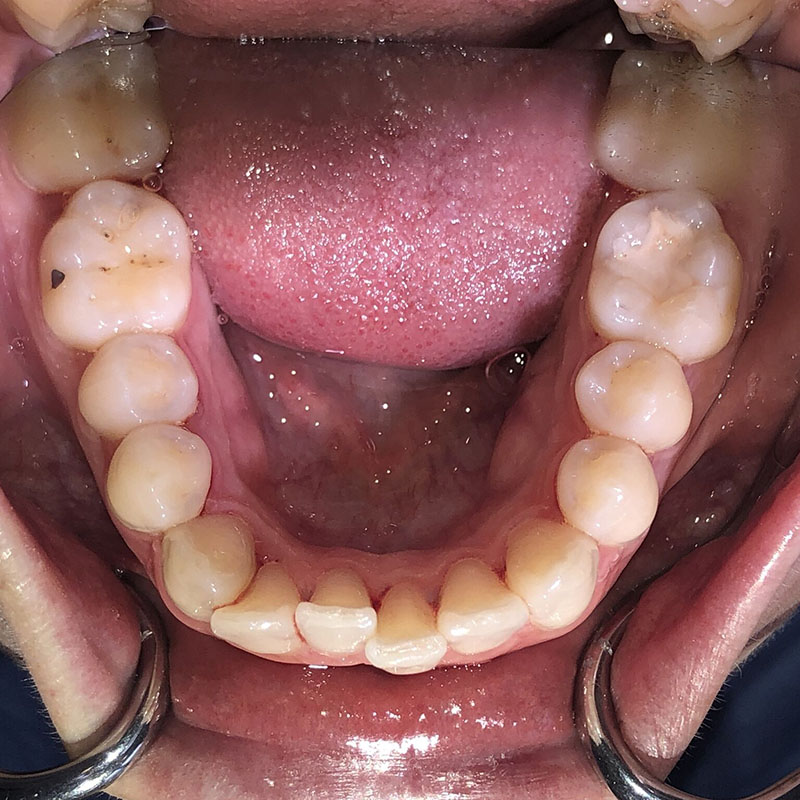

Patiente de 34 ans venue au cabinet pour une réhabilitation de son sourire suite à une récidive de son traitement d’orthodontie survenue pendant son adolescence, à cause du non-remplacement de sa contention perdue. Elle avait eu dans le passé une proposition de traitement par facettes pour réaliser l’alignement qu’elle avait refusé, ne voulant pas que l’on touche à ses dents.

À l’examen clinique, la patiente est en classe I d’Angle molaire bilatérale, indication idéale pour les traitements d’alignement simples que peuvent réaliser les omnipraticiens formés à cette thérapeutique.

Aucune autre pathologie ni problème dentaire ne furent relevés, en dehors d’un nettoyage préalable.